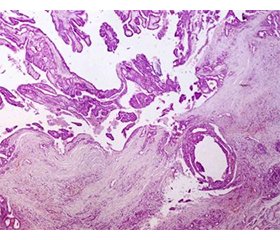

Папілярна карцинома щитоподібної залози (ПКЩЗ) є найпоширенішою формою раку щитоподібної залози в дітей, хоча її маніфестація в цій віковій групі залишається рідкісною. ПКЩЗ, незважаючи на хороший прогноз, у дітей може мати більш агресивний перебіг, ніж у дорослих. Діагностичний процес полягає в проведенні фізикального огляду, ультразвукового дослідження (УЗД) і тонкоголкової аспіраційної пункційної біопсії (ТАПБ) для цитологічної оцінки за допомогою системи Bethesda. Стандартним методом лікування ПКЩЗ є хірургічне втручання — лобектомія або тотальна тиреоїдектомія залежно від поширення захворювання, цитологічних знахідок та профілю пацієнта. Наведено клінічний випадок підозри на вузол щитоподібної залози в 9-річної дівчинки, лікування якої за допомогою лобектомії було успішним. Під час УЗД виявилено щільний, гіпоехогенний вузол із мікрокальцинатами в правій частці щитоподібної залози. За даними ТАПБ отримано результат: категорія V згідно з класифікацією Bethesda (підозра на папілярну карциному). Після комплексного обстеження медичною командою (ендокринолог, хірург, цитопатолог, рентгенолог, дитячий онколог) було прийнято рішення про проведення правобічної лобектомії щитоподібної залози як із діагностичною, так і терапевтичною метою. Під час операції виявлено чітко відмежований вузол без ознак інвазії в навколишні тканини. Гістопатологічний аналіз підтвердив діагноз ПКЩЗ, фолікулярний варіант, без судинної або екстратиреоїдної інвазії та без метастазів у досліджуваних лімфатичних вузлах. Ці дані свідчать про локалізовану форму захворювання з відмінним прогнозом. Після втручання пацієнтка виписана з клініки без ускладнень: життєво важливі параметри залишалися стабільними, не було жодних ознак кровотечі або місцевої інфекції, контрольне УЗД через 6 тижнів не показало залишкових утворень, а структура лівої частки та навколишніх тканин була нормальною. Не виникло потреби в тотальній тиреоїдектомії або терапії радіоактивним йодом відповідно до чинних протоколів щодо локалізованих випадків. Обговорюється важливість ранньої діагностики, відповідного хірургічного лікування й ретельного клінічного спостереження, а також роль багатопрофільної команди у веденні дітей із раком ендокринної системи.

Papillary thyroid carcinoma (PTC) is the most common form of thyroid cancer in children, although its presentation in this age group remains rare. PTC, despite having a good prognosis, can present more aggressively in children than in adults. Diagnosis typically begins with physical examination and ultrasound, followed by fine-needle aspiration biopsy (FNAB) for cytological assessment using the Bethesda system. Standard treatment for PTC is surgery — lobectomy or total thyroidectomy depending on disease spread, cytological findings, and patient profile. This paper presents the clinical case of a 9-year-old female patient with a suspicious thyroid nodule, successfully treated through thyroid lobectomy. Ultrasound revealed a solid, hypoechoic nodule with microcalcifications in the right thyroid lobe. FNAB returned a Bethesda V classification, raising suspicion for papillary carcinoma. After a multidisciplinary evaluation by the medical team (endocrinologist, surgeon, cytopathologist, radiologist, pediatric oncologist), a right thyroid lobectomy was decided upon for both diagnostic and therapeutic purposes. During surgery, a well-confined nodule was identified with no apparent invasion into surrounding tissues. Histopathological analysis confirmed papillary thyroid carcinoma, follicular variant, no vascular or extrathyroidal invasion, no metastases in the examined lymph nodes. These findings suggested a localized disease form with an excellent prognosis. Following the intervention, the patient recovered without complications: vital parameters remained stable, with no signs of bleeding or local infection; follow-up ultrasound at 6 weeks showed no residual formations, and normal structure of the left lobe and surrounding tissues. There was no need for total thyroidectomy or radioactive iodine therapy, in accordance with current protocols for localized cases. The importance of early diagnosis, appropriate surgical treatment, and careful clinical follow-up is discussed, as well as the role of a multidisciplinary team in managing pediatric endocrine oncology cases.